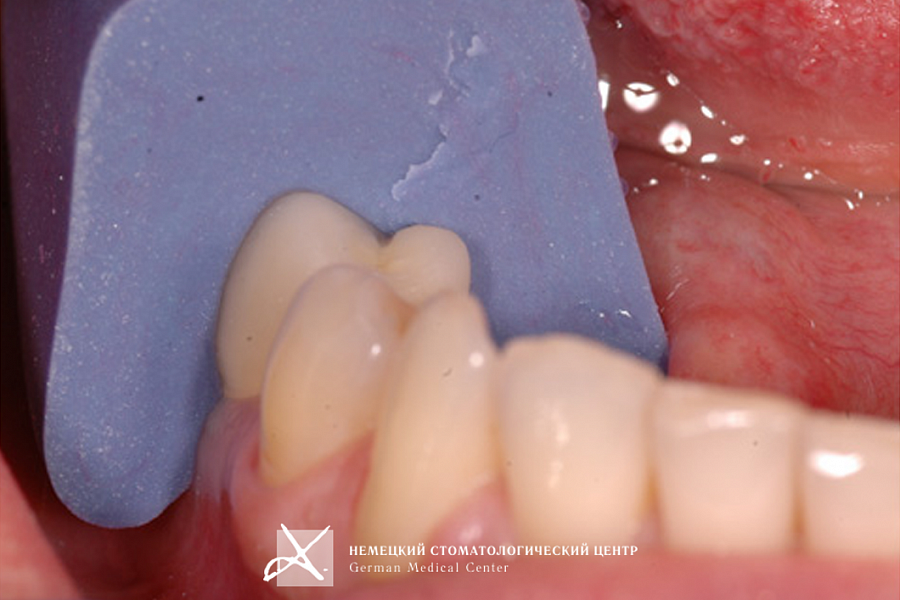

- На индивидуальный абатмент зацементирована эстетическая керамическая коронка.